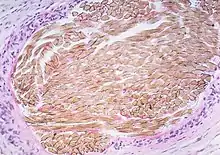

| Picture of a granuloma (without necrosis) as seen through a microscope on a glass slide: The tissue on the slide is stained with two standard dyes (hematoxylin: blue, eosin: pink) to make it visible. The granuloma in this picture was found in a lymph node of a patient with a Mycobacterium avium infection. | |

Macrophages (specifically histiocytes) are the cells that define a granuloma. They often fuse to form multinucleated giant cells (Langhans giant cell).[7] The macrophages in granulomas are often referred to as "epithelioid". This term refers to the vague resemblance of these macrophages to epithelial cells. Epithelioid macrophages differ from ordinary macrophages in that they have elongated nuclei that often resemble the sole of a slipper or shoe. They also have larger nuclei than ordinary macrophages, and their cytoplasm is typically pinker when stained with eosin. These changes are thought to be a consequence of "activation" of the macrophage by the offending antigen.

The other key term in the above definition is the word "organized" which refers to a tight, ball-like formation. The macrophages in these formations are typically so tightly clustered that the borders of individual cells are difficult to appreciate. Loosely dispersed macrophages are not considered to be granulomas.

An important feature of granulomas is whether or not they contain necrosis, which refers to dead cells that, under the microscope, appear as a mass of formless debris with no nuclei present. A related term, caseation (literally: turning to cheese) refers to a form of necrosis that, to the unaided eye, appears cheese-like ("caseous"), and is typically a feature of the granulomas of tuberculosis. The identification of necrosis in granulomas is important because granulomas with necrosis tend to have infectious causes.[2] Several exceptions to this general rule exist, but it nevertheless remains useful in day-to-day diagnostic pathology.